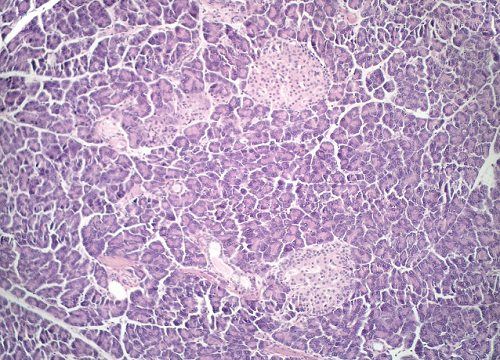

Question 19

Question

Label this image

Image:

aa46be85-fddf-4f03-92c3-77618cfbb1e3 (image/png)

Answer

Pancreas